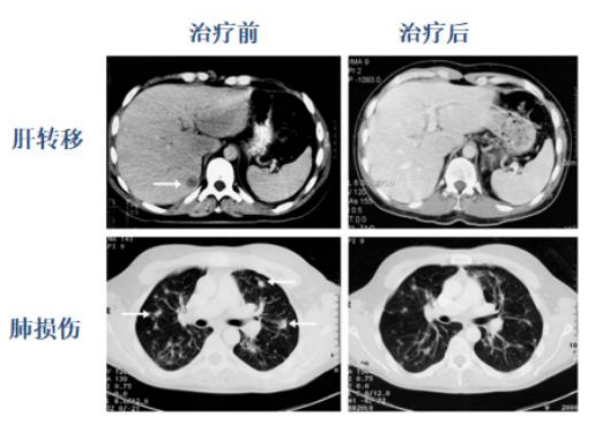

44例晚期癌症患者,经过各种常规治疗后出现肺、肝转移,单个病灶<1cm,经过一年的NKT治疗干预,CT评效,显效率接近70%!

NK-T回输治疗后肺癌病人肿瘤指标下降,肝转移完全消退(上),肺损伤明显减少(下),箭头所示回输治疗之前的损伤部。